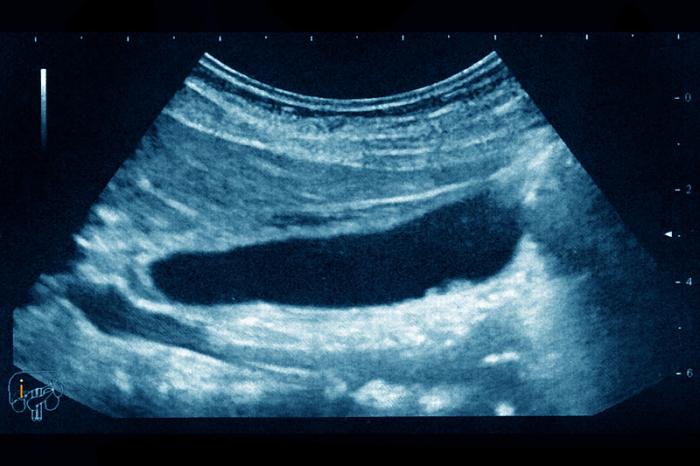

胆汁从肝脏制造并送进胆囊储存,当进食时胆囊会收缩、将胆汁排入到十二指肠,促进消化和吸收。据中医部医师的解释,正常情况的胆汁流动方向应是往下流,却反向跑到胃或食道的关系,透过胃镜检查则会看到胃壁瀰漫黄色胆液。逆流的原因可分原发性及继发性,胆汁分泌过多、大量释放或幽门括约肌结构异常有关。